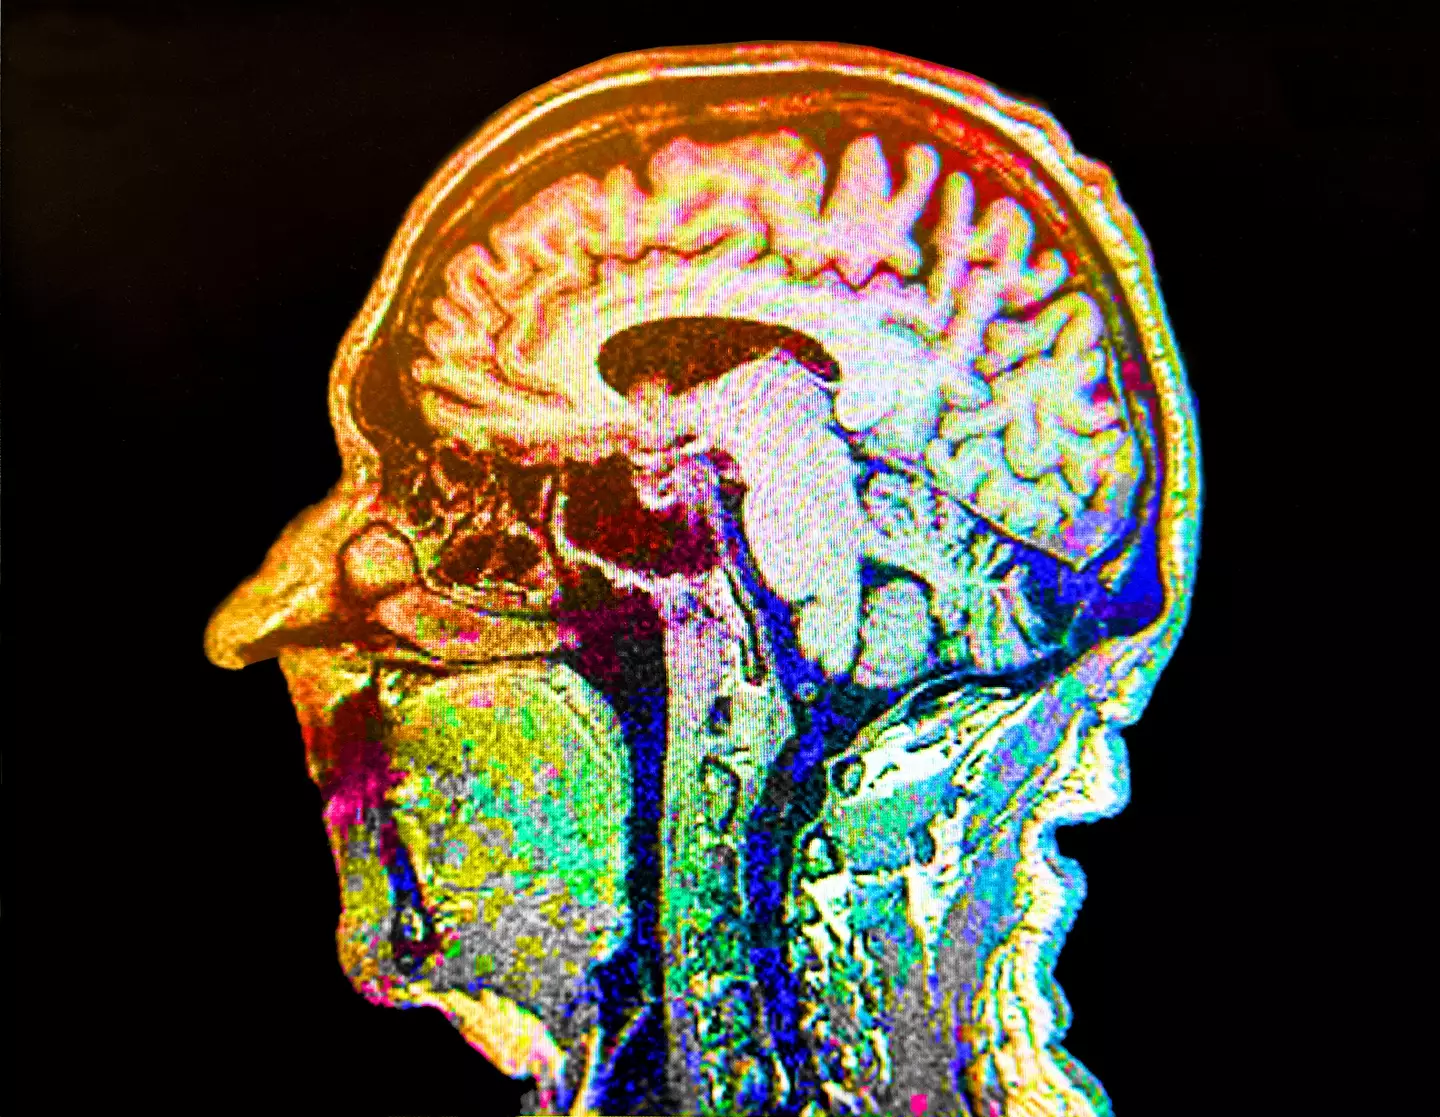

Alzheimer's is a brain disorder that causes memory loss, confusion, and changes in behaviour, and is the most common form of dementia in older people.